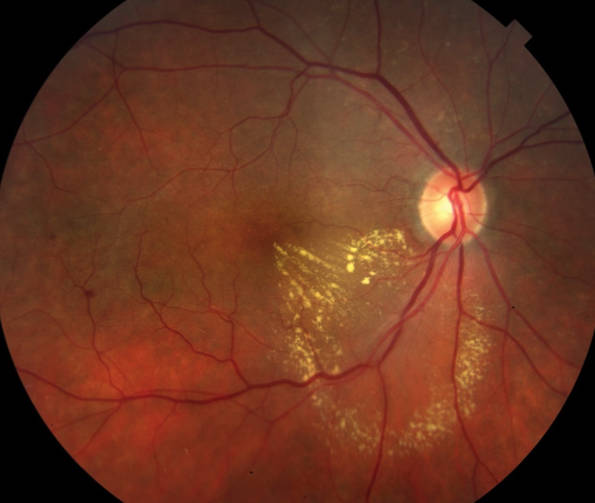

Drusenoid Detachment of RPE

Histologic and Optical Coherence Tomographic Correlates in Drusenoid Pigment Epithelium Detachment in Age-Related Macular Degeneration.

Balaratnasingam C, Messinger JD, Sloan KR, Yannuzzi LA, Freund KB, Curcio CA.

Ophthalmology. 2017 May;124(5):644-656. doi: 10.1016/j.ophtha.2016.12.034. Epub 2017 Jan 30.